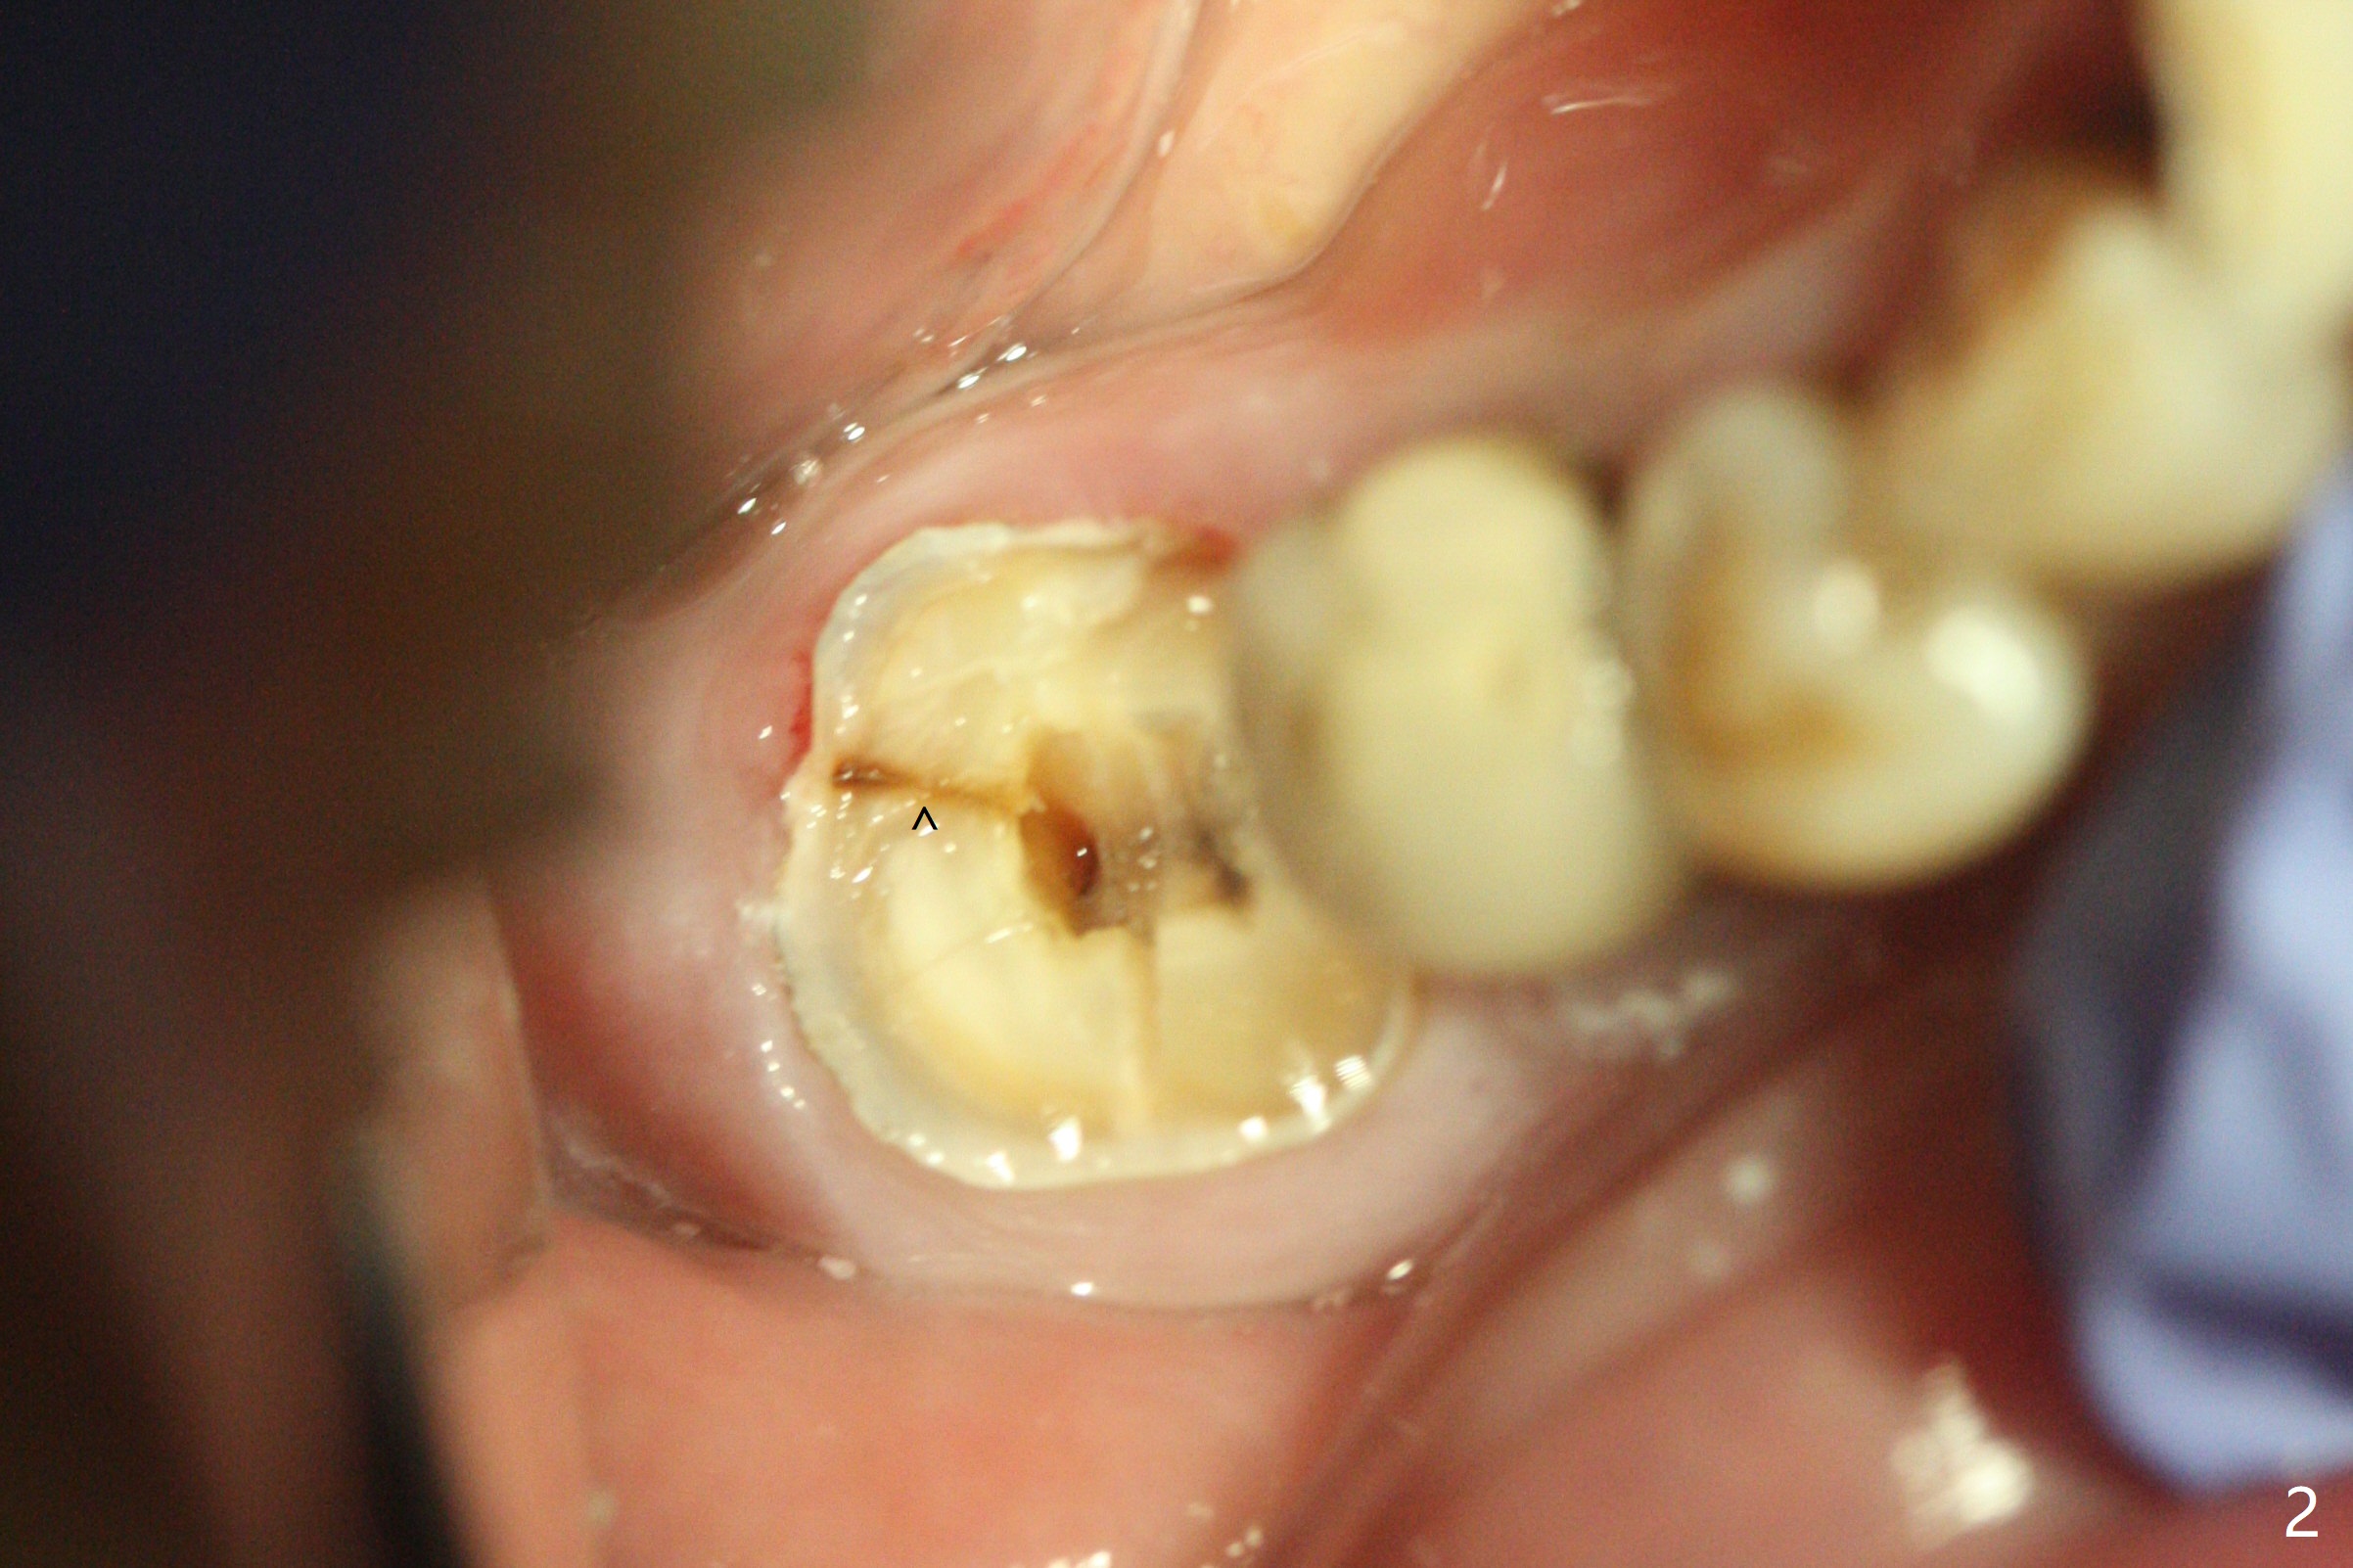

A 59-year-old woman with severe pain and mobility at #30 returns to clinic for extraction and implant on emergency basis (Fig.1 ^: crazing line). To prevent osteotomy deviation off the septum, the crown is sectioned (Fig.2) and the coronal end of the septum is exposed. In fact the initial osteotomy is blind (Fig.3). After increasing the access (Fig.4), trying to change trajectory and increasing the depth and diameter of the osteotomy, the trajectory deviates to the distal socket (Fig.5). Following root extraction, debridement of the sockets and minor trajectory change, a 4x11 mm dummy implant is placed (Fig.6). With a drastic change in osteotomy, the dummy implant position is somewhat acceptable with a 5.2x4 mm planning abutment (Fig.7 P). After placement of bone graft around the 4.5x11 mm final implant to enhance stability, a 5.5x4(3) mm definitive abutment is placed in a restorable position (Fig.8). The implant turns while the abutment screw is hand tightened. Since there is an apical space (Fig.8 <), the implant is then placed ~ 1mm deeper with ~ 30 Ncm (Fig.9). A longer cuffed abutment is inserted and more bone graft is placed (*). In summary, roots in the sockets do not seem to help free hand osteotomy in the lower 1st molar. It is also difficult to control pain during acute infection. Block anesthesia has to be administered, increasing the chance of nerve injury. Either guided surgery or delayed implant should be conducted. There is no postop paresthesia, although the buccal gingiva is slightly erythematou, edematous and tender 1 week posotp. Oral Amoxicillin is prescribed for one more week. The keratinized gingiva (Fig.10 ^) and the papilla (*) are maintained in place around the immediate provisional (P) 2 months 20 days postop. The soft tissue remains normal 4 months postop (Fig.11) and immediate pre cementation (Fig.12).